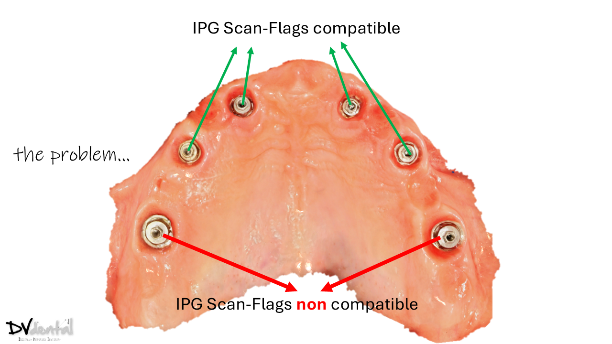

In this case, we encountered a problem: while the MUA of the four anterior implants were compatible with the IPG scan bodies, the two posterior implants were not compatible with the IPG scan bodies. Therefore, we will scan the two posterior implants using normal 3D reconstruction technology (in the soft tissue scan, placing two standard scan bodies on the MUA of the two posterior implants) and then scan the anterior implants with IPG technology (placing the IPG scan bodies on the MUA of the four anterior implants).

Fig 7: In the same arch, four MUAs are coded scanbody compatible, while the rest two MUAs are coded scanbody non compatible.